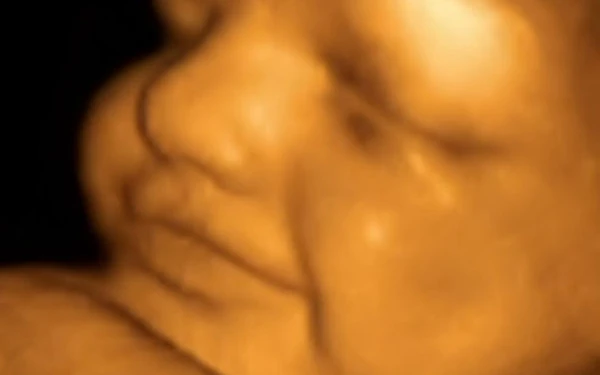

- Από τον 7ο μήνα της εγκυμοσύνης, το μωρό θα αρχίσει να ονειρεύεται καθώς ο εγκέφαλος έχει αναπτυχθεί αρκετά για να ξεκινήσει το στάδιο του REM ύπνου. Στη φάση αυτή του ύπνου, τα υψηλότερα κέντρα του εγκεφάλου ενεργοποιούνται από βαθύτερες περιοχές. Κατά τη διάρκεια του REM ύπνου, το έμβρυο δεν έχει τον έλεγχο της κίνησης των μυών του, επομένως έχει τη δυνατότητα να κάνει κινήσεις αντανακλαστικά.

- Όσο πιο μικρό είναι ένα παιδί τόσο πιο πολύ ονειρεύεται. Μάλιστα το 90% του ύπνου των πρόωρα γεννημένων βρεφών καταλαμβάνεται από το στάδιο REM. Τα έμβρυα ονειρεύονται ακόμα περισσότερο, αλλά παραμένει μυστήριο το περιεχόμενό τους. Πιθανόν να είναι ένα συνδυασμός από λάμψεις και ήχους.

- Το έμβρυο πολλές φορές μοιάζει να χαμογελά μέσα στον ύπνο του. Αυτό συμβαίνει γιατί οι μύες του προσώπου κινούνται αντανακλαστικά.